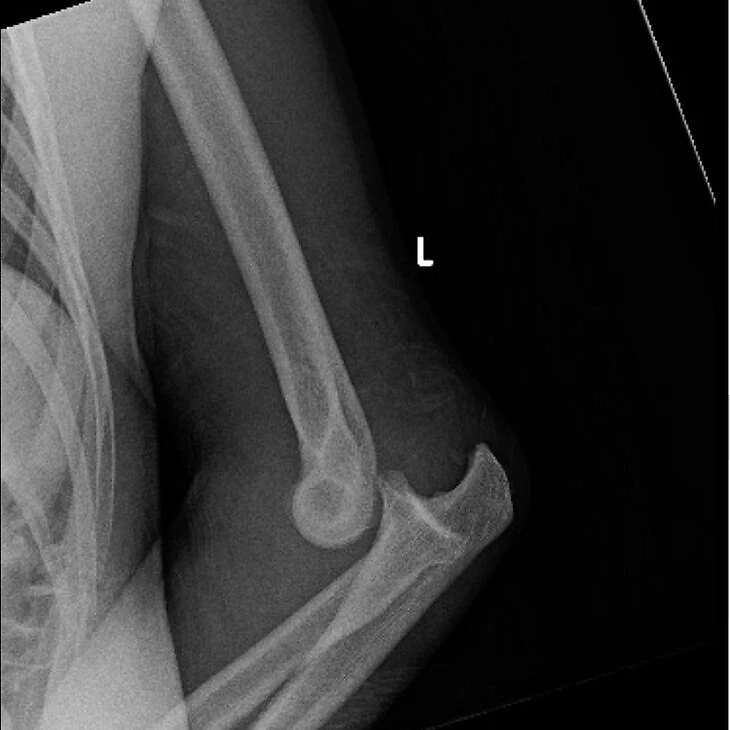

За опубликованный рентген Дану Уайта назвали дикарем, а Дудакову призывают отказаться от победы

После боя президент UFC Дана Уайт, указав аккаунт Нуньес, опубликовал в инстаграме эпизод с падением и рентген травмированной руки: «Жесть».